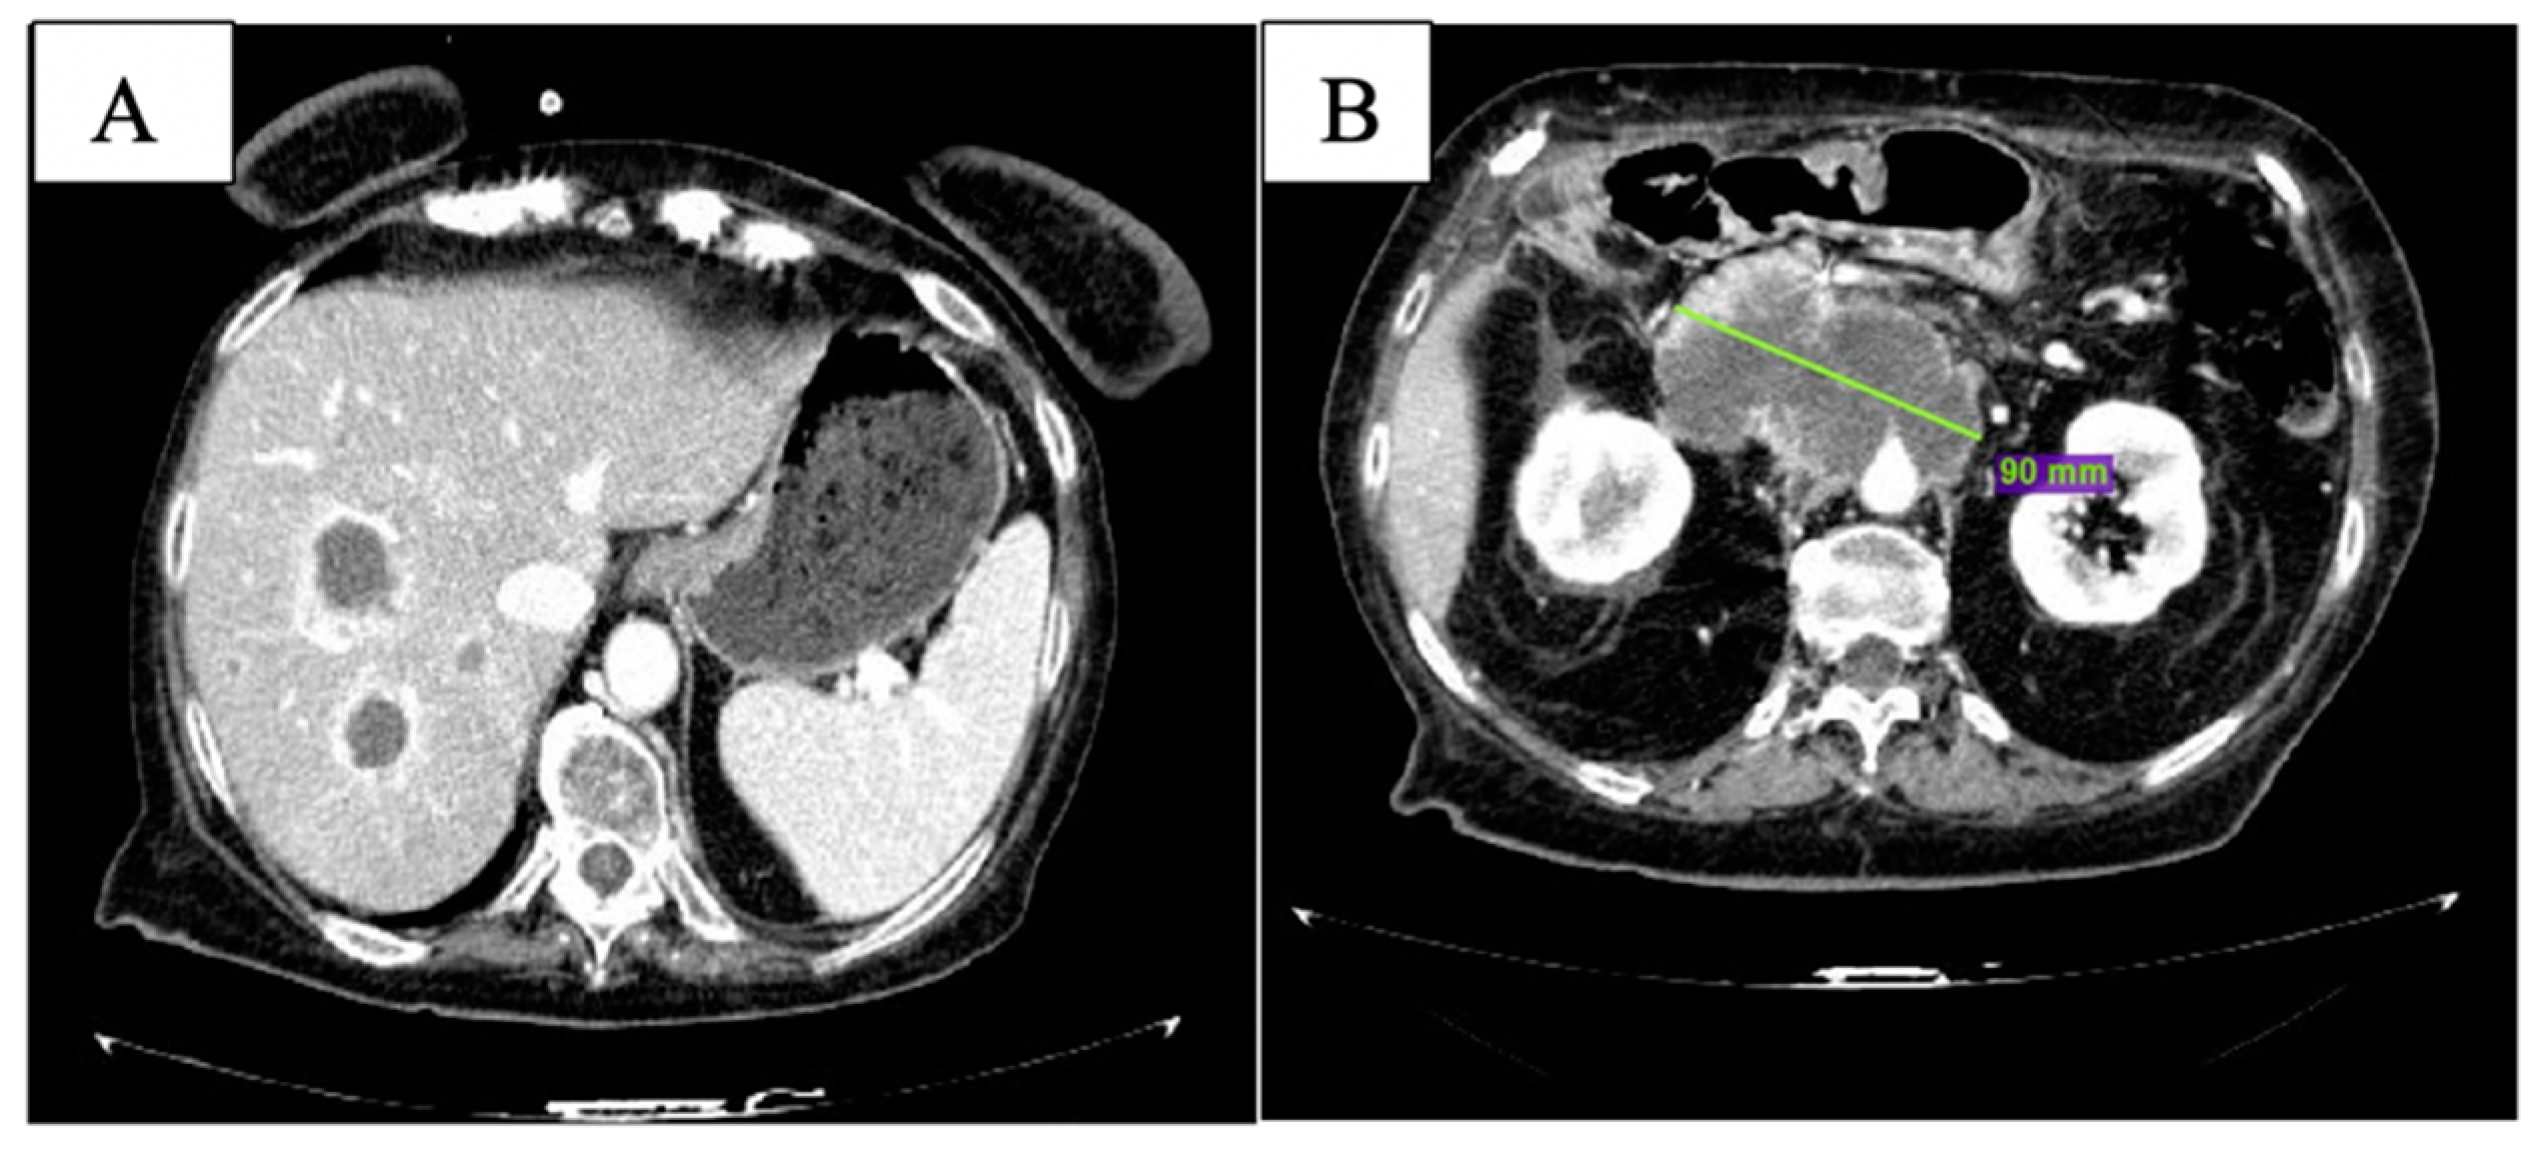

At CT scan in January 2019, both pulmonary and nodal lesions were augmented in volume; new hepatic lesions were also documented (Figure 1).

Figure 1.

Baseline CT scan showing nodular lesion in inferior lobe of the right lung (A), hepatic lesion in the 8th segment (B) and peripancreatic tissue (C).